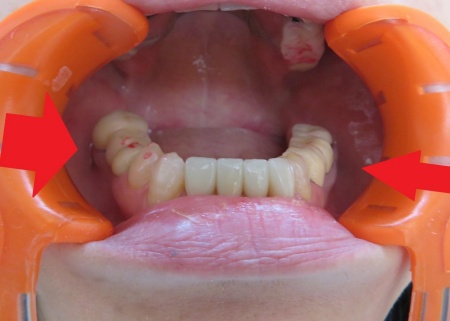

まず、入れ歯を装着した状態で噛み合う面に1mm程度、即時重合レジンと呼ばれる歯科用プラスチックを盛り、実際に噛んでいただきながら適切な噛み合わせの位置を慎重に確認して記録します。

即時重合レジンは、粉と液を混ぜると数分で硬化する性質がある材料です。

プラスチックの硬化後は、はみ出した余分な部分を丁寧に削り取り、上下の歯が自然に噛み合うように調整を行いながら、表面を丁寧に研磨しました。

左側にレジンを盛り、噛み合わせを記録しました。

奥歯でしっかり噛めることを確認しました。

右側にもレジンを盛り、噛み合わせを記録します。